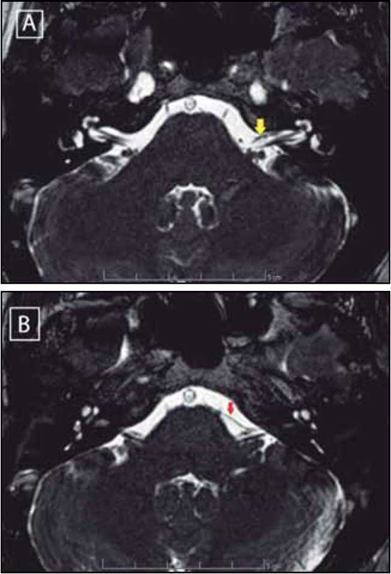

Es revalorada por otorrinonaringología con los resultados de audiometría tonal, revelando normoacusia bilateral, timpanometría con curvas de tipo A normal bilaterales, al examen físico con otoscopia y rinoscopia normal, sin alteraciones otoneurológicas aparentes, diadococinesis conservada, sin evaluar Romberg y Unterberguer por limitación para la bipedestación de la paciente, nistagmos presentes multidireccionales, se palpan contracturas cervicales dolorosas al tacto y se sospecha más un cuadro por tensión muscular. Se realiza la resonancia magnética nuclear (RMN) cerebral contrastada, la cual revela un asa vascular en el ángulo pontocerebeloso izquierdo que ingresa al CAI en menos de 50% de su longitud, entre el complejo del VII-VIII par craneal, sin angulación de éstos por asa vascular de tipo II, posiblemente de la AICA (Figura 1).

Con la RMN cerebral es posible identificar detalles finos, tales como asas vasculares en el CAI 10,11, de igual forma a partir de ella es posible visualizar estructuras vasculares y neuronales en el ángulo pontocerebeloso y determinar la relación entre el nervio vestíbulococlear y la vasculatura a su alrededor 8. En la Tabla 2 se observa la clasificación de las asas vasculares. Aproximadamente en 9% de los casos, las asas vasculares de la AICA se extienden más de 50% de la longitud del CAI 10 y 12.3 % se producen dentro del CAI según estudios postmortem 11. Los principales síntomas ocasionados por una asa vascular de la AICA son acúfenos (65%), con una incidencia de 7-12% en la población general, y cuya forma de presentación en su mayoría es pulsátil 10.